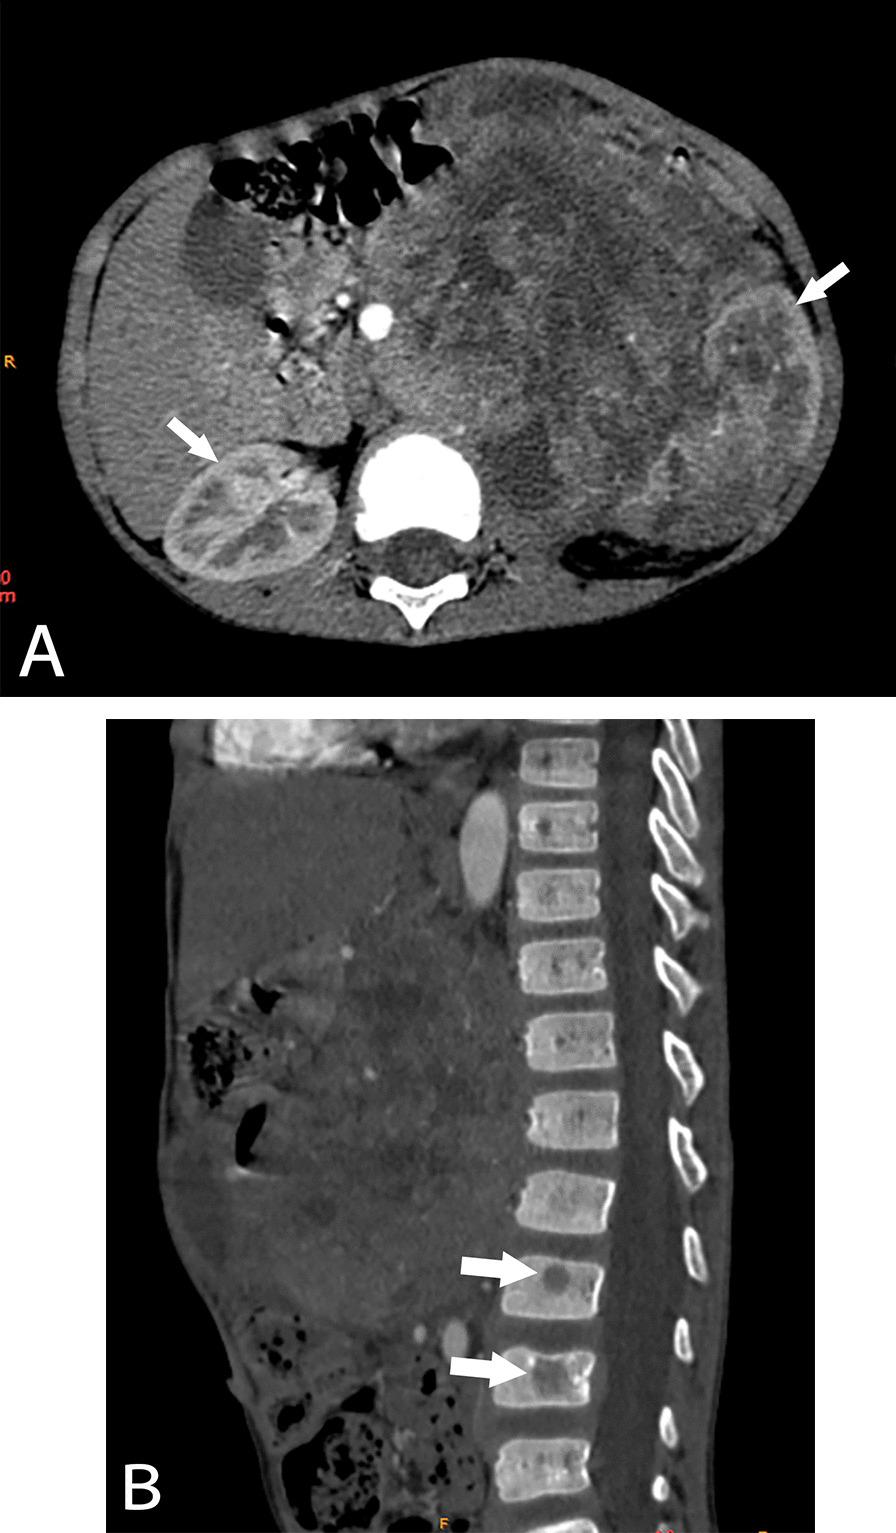

The study included CCSK (22 cases), MRTK (27 cases) and RCC (16 cases). There were no significant differences observed among the sex ratios of CCSK, MRTK and RCC (all P > 0.05). Among the three tumors, the onset age of MRTK patients was the smallest, while that of RCC patients was the largest (all P < 0.05). The tumor diameter of CCSK was larger than that of MRTK and RCC (all P < 0.001). For hemorrhage and necrosis, the proportion of MRTK patients was larger than that of the other two tumors (P = 0.017). For calcification in tumors, the proportion of calcification in RCC was highest (P = 0.009). Only MRTK showed subcapsular fluid (P < 0.001). In the arterial phase, the proportion of slight enhancement in RCC was lower than that in the other two tumors (P = 0.007), and the proportion of marked enhancement was the highest (P = 0.002). In the venous phase, the proportion of slight enhancement in RCC was lower than that in the other two tumors (P < 0.001). Only CCSK had bone metastasis. There was no liver and lung metastasis in RCC.

NWTs have their own imaging and clinical manifestations. CCSK can cause vertebral metastasis, MRTK can cause subcapsular effusion, and RCC tumor density is usually high and calcification. These diagnostic points can play a role in clinical diagnosis.